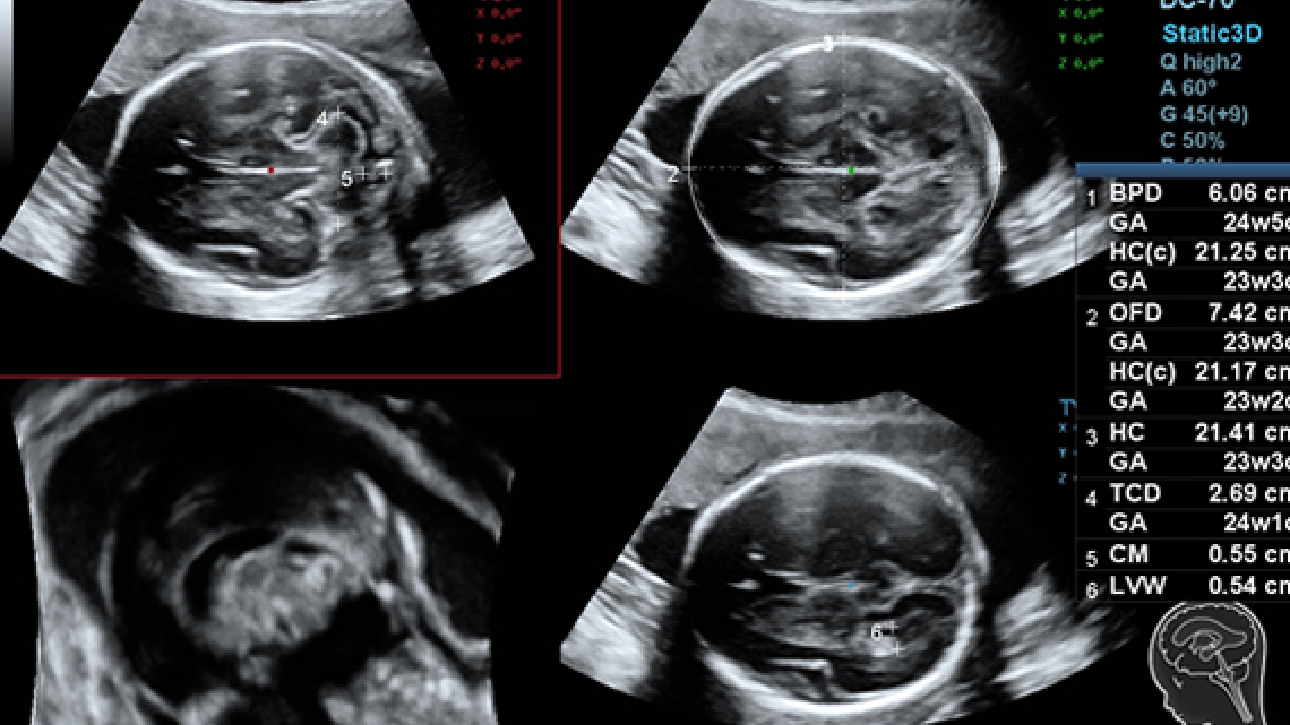

ImĂĄgenes clĂnicas